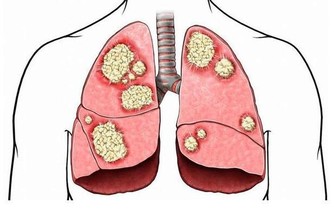

醫生認為,牛奶中的 beta-CM-7 蛋白會造成鼻涕阻塞,尤其是有肺病史的人群。

雖然目前這一結論尚未得到證實,

但如果你為了安全起見,盡量不要食用牛奶及其他乳製品。

慢性鼻竇炎患者除了有上述症狀外,還會伴有咳嗽、支氣管炎和哮喘。